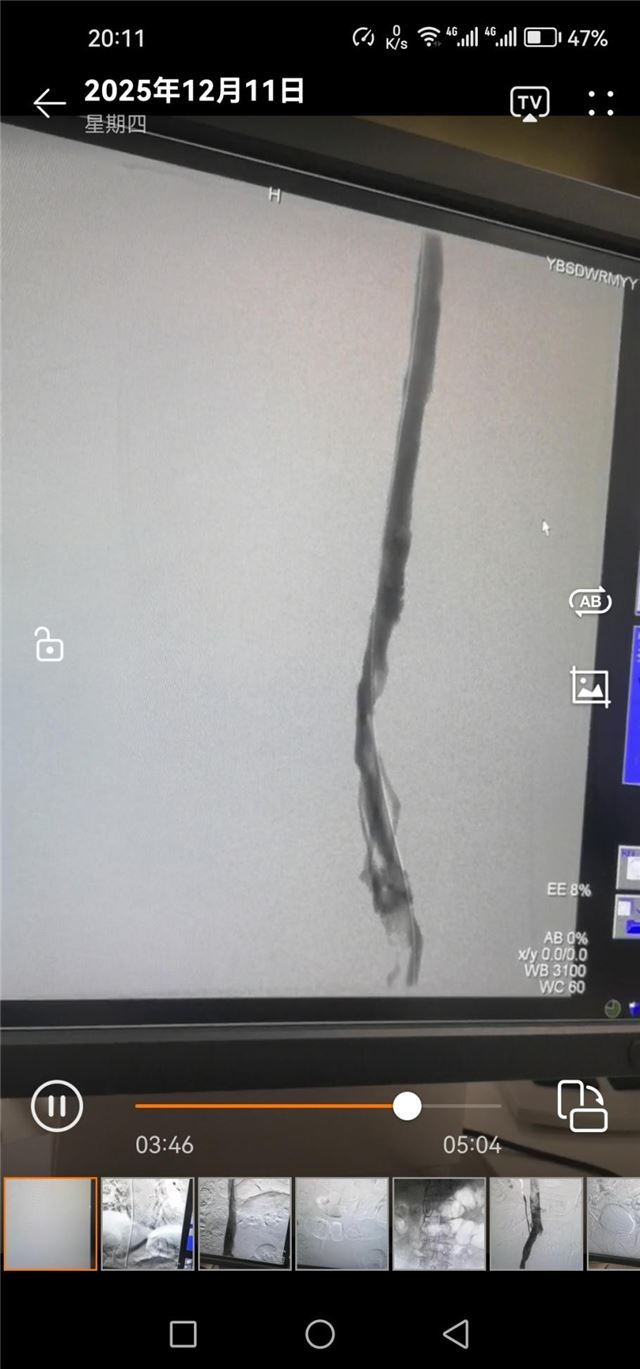

手术后下肢深静脉造影

相较于传统治疗方式,介入治疗具有微创、高效、精准、恢复快等显著优势:手术创口仅几毫米,大大降低了患者的痛苦和感染风险;能直接清除或溶解血栓,快速缓解患肢肿胀疼痛症状;术后患者卧床时间短,可更早下床活动,有效减少深静脉血栓后综合征等远期并发症的发生。

近两个月来,团队已成功为多名不同分型的下肢深静脉血栓患者实施介入手术。从术前精准评估、制定个性化方案,到术中精细操作、严密监测,再到术后规范抗凝、康复指导,医护人员全程为患者保驾护航。术后患者患肢肿胀疼痛症状均迅速缓解,恢复效果远超预期,多名患者已顺利康复出院,赢得了患者及家属的高度赞誉。